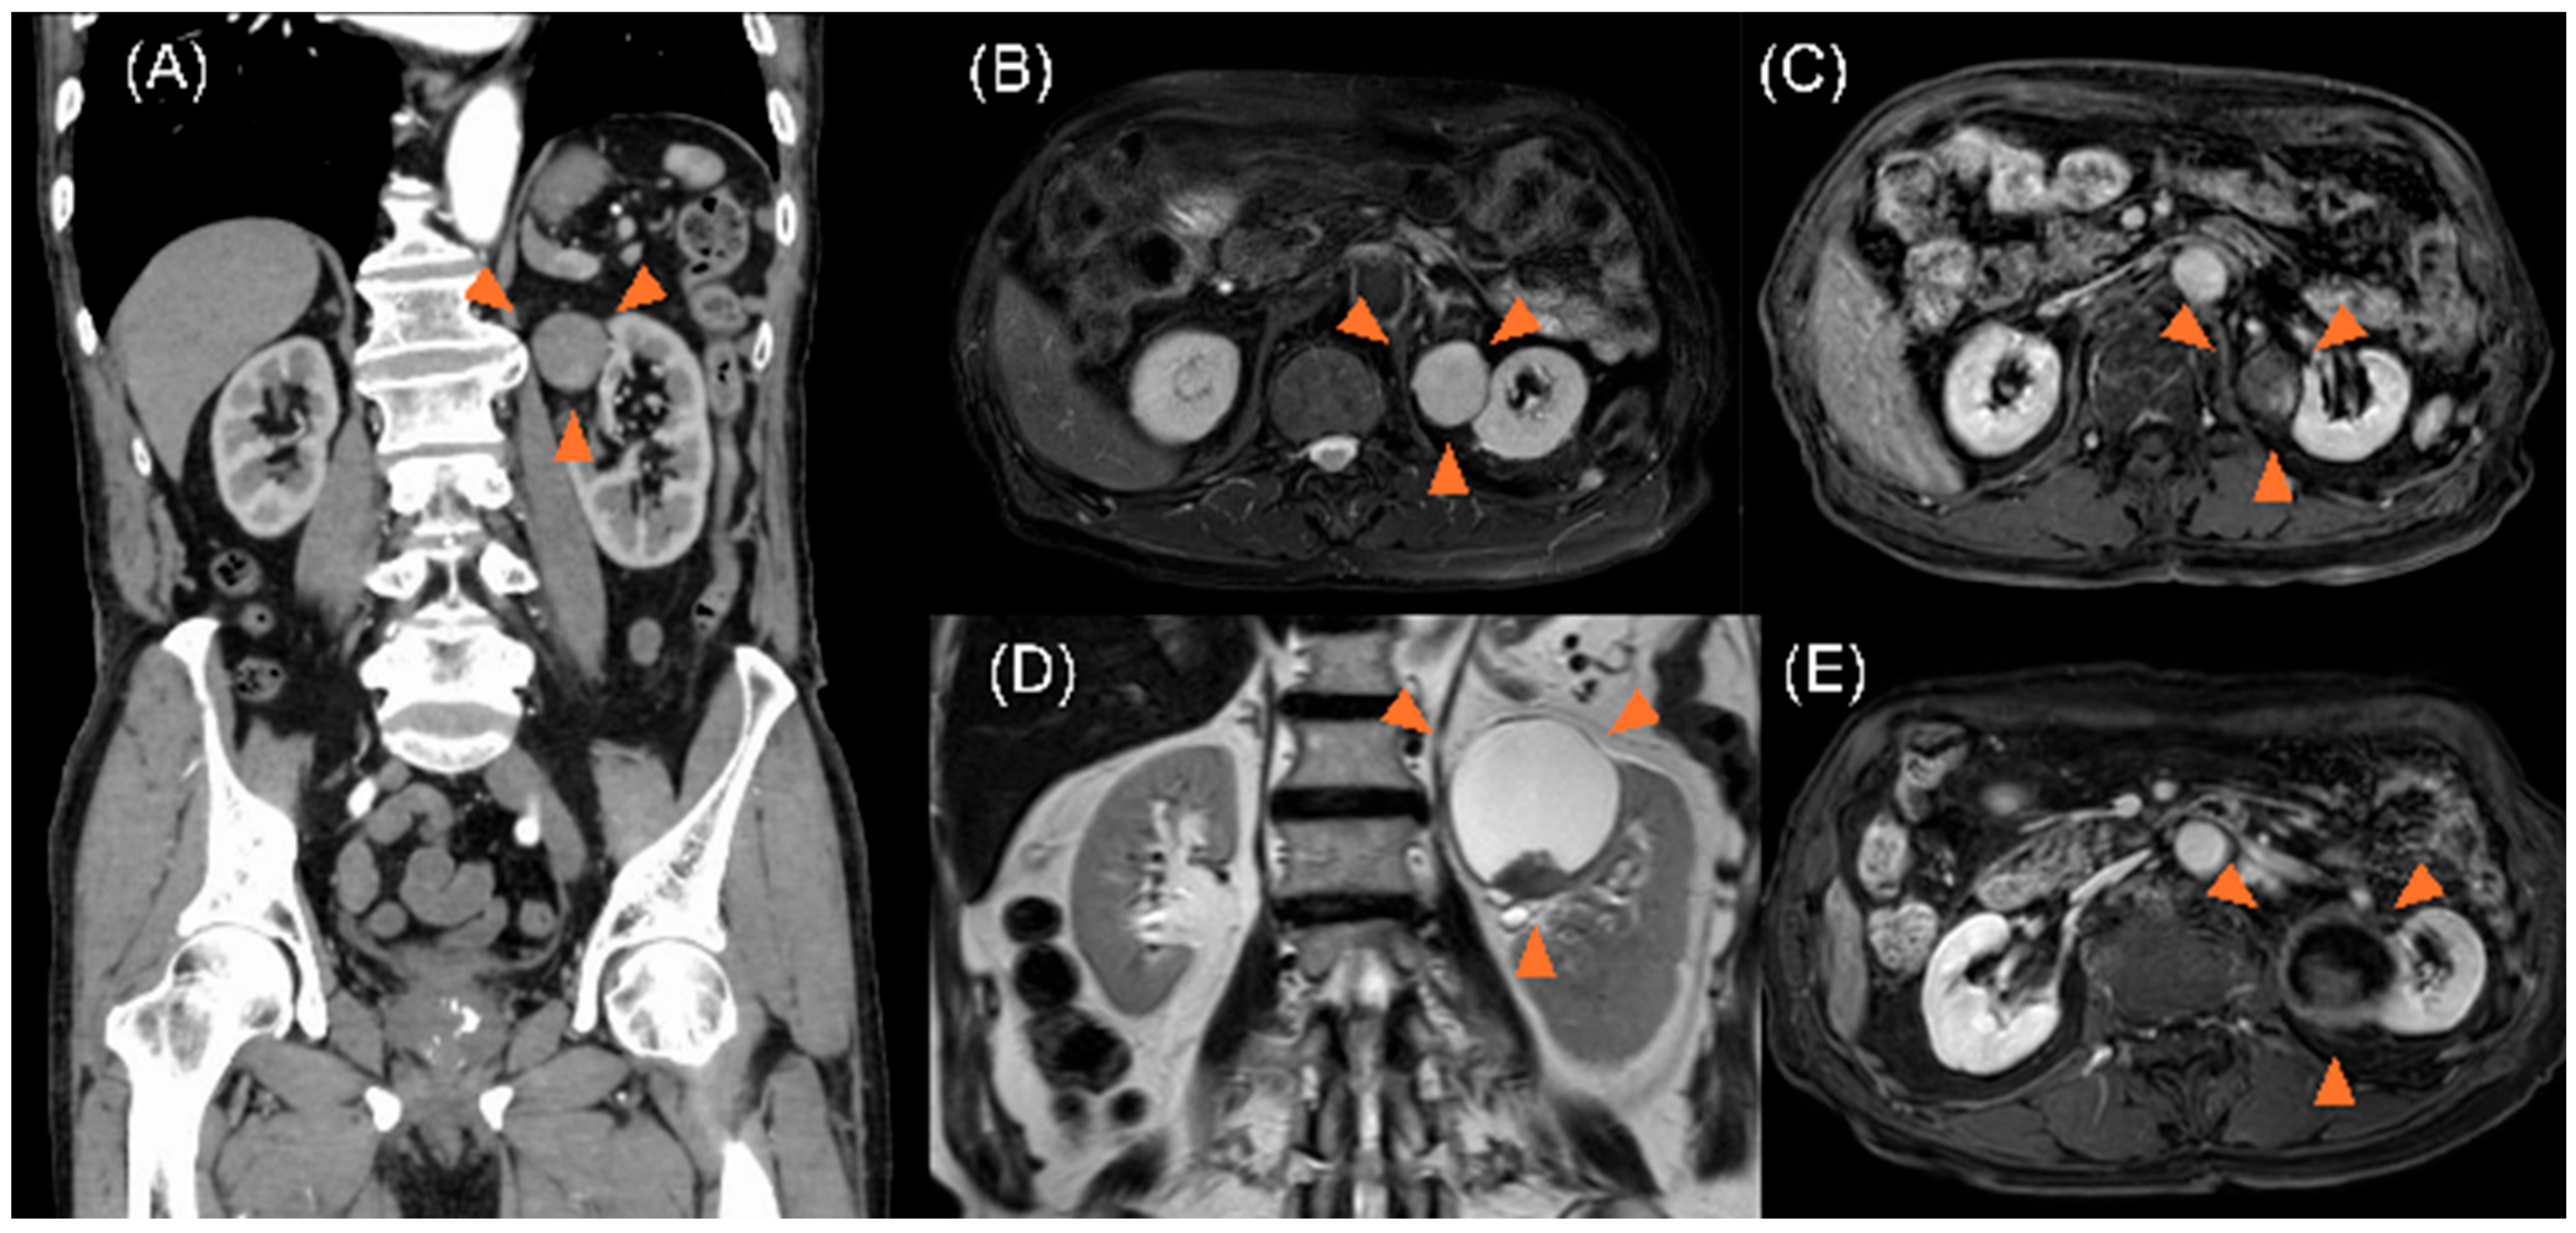

2. Case Description